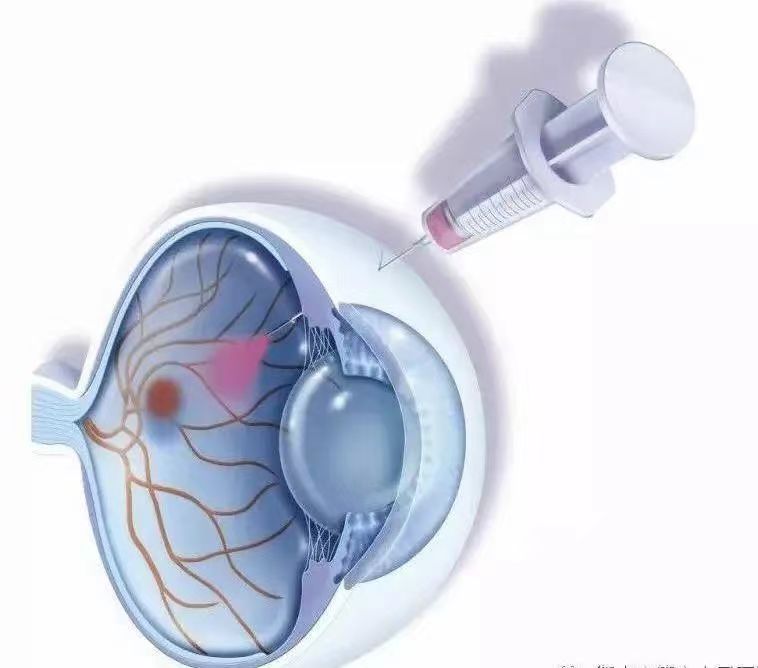

藥物治療:通過眼內打針即玻璃體腔局部注射抗VEGF藥物、糖皮質激素治療糖性黃斑水腫。局部抗VEGF藥物需在專業眼科醫生指導下遵醫囑按需注射。

眼內打針是什么意思?

眼內打針,多指向眼內玻璃體腔內注射抗血管內皮生長因子(VEGF)藥物。VEGF是參與糖尿病黃斑水腫病理生理過程的一個重要因子,缺氧、高血糖等病理條件可能導致VEGF上調,進而引起滲漏、血管增生等病理過程。已有大量證據顯示抗VEGF治療在糖尿病黃斑水腫治療中的療效。目前,臨床常用抗VEGF制劑包括雷珠單抗、阿柏西普、康柏西普等。玻璃體腔內注射抗VEGF適用于威脅視力的糖尿病性黃斑水腫。